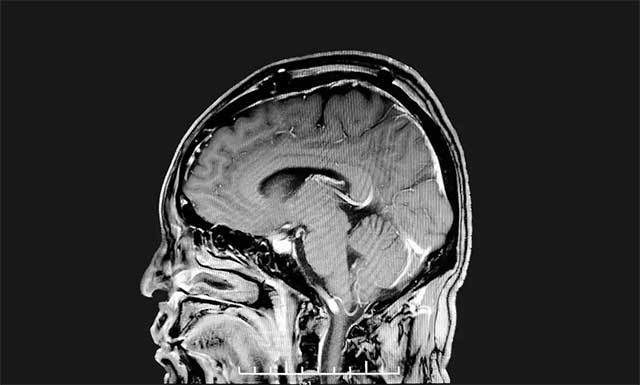

▲ 腫瘤已被切除

沈建康教授聚精會神、抽絲剝繭般一點點游離腫瘤包裹的靜脈,再以超聲刀切除殘余腫瘤組織,歷時四個多小時,手術(shù)順利完成。術(shù)后經(jīng)病理分析,該腫瘤為腦膜瘤,與術(shù)前診斷相一致。